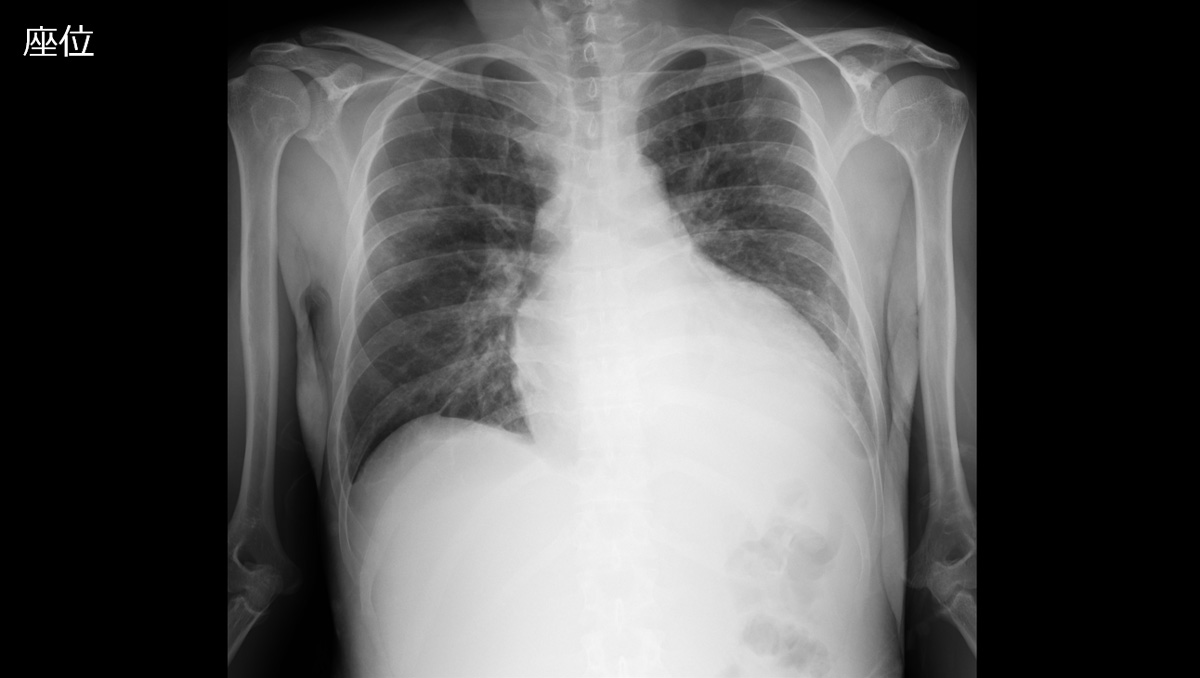

症例1:28歳男性

- 【主訴】

- 体動困難、呂律不良

- 【現病歴】

-

- 4か月ほど前から歩行時の息切れあり、1か月前から下肢の疼痛が出現、1週間前からはベッド上で生活していた。

- 3日前から呂律が緩慢となり、増悪したため、父親が救急要請。

- 医療機関の受診歴なし

- 高校卒業後は就職せず、自宅でゲームをする時間が長かった。

- 救急隊より、自宅はゴミ屋敷の状態であった、と。

- 【既往歴】

- JCS I-3

BT 37.6℃, BP 147/58mmHg, HR 120/min, SpO2 99% - 【血液検査】

- WBC 11000/µL, Hb 9.7g/dL, CRP 4.94mg/dL

低血糖なし、電解質異常なし、甲状腺機能異常なし

COVID-19とインフルエンザは陰性